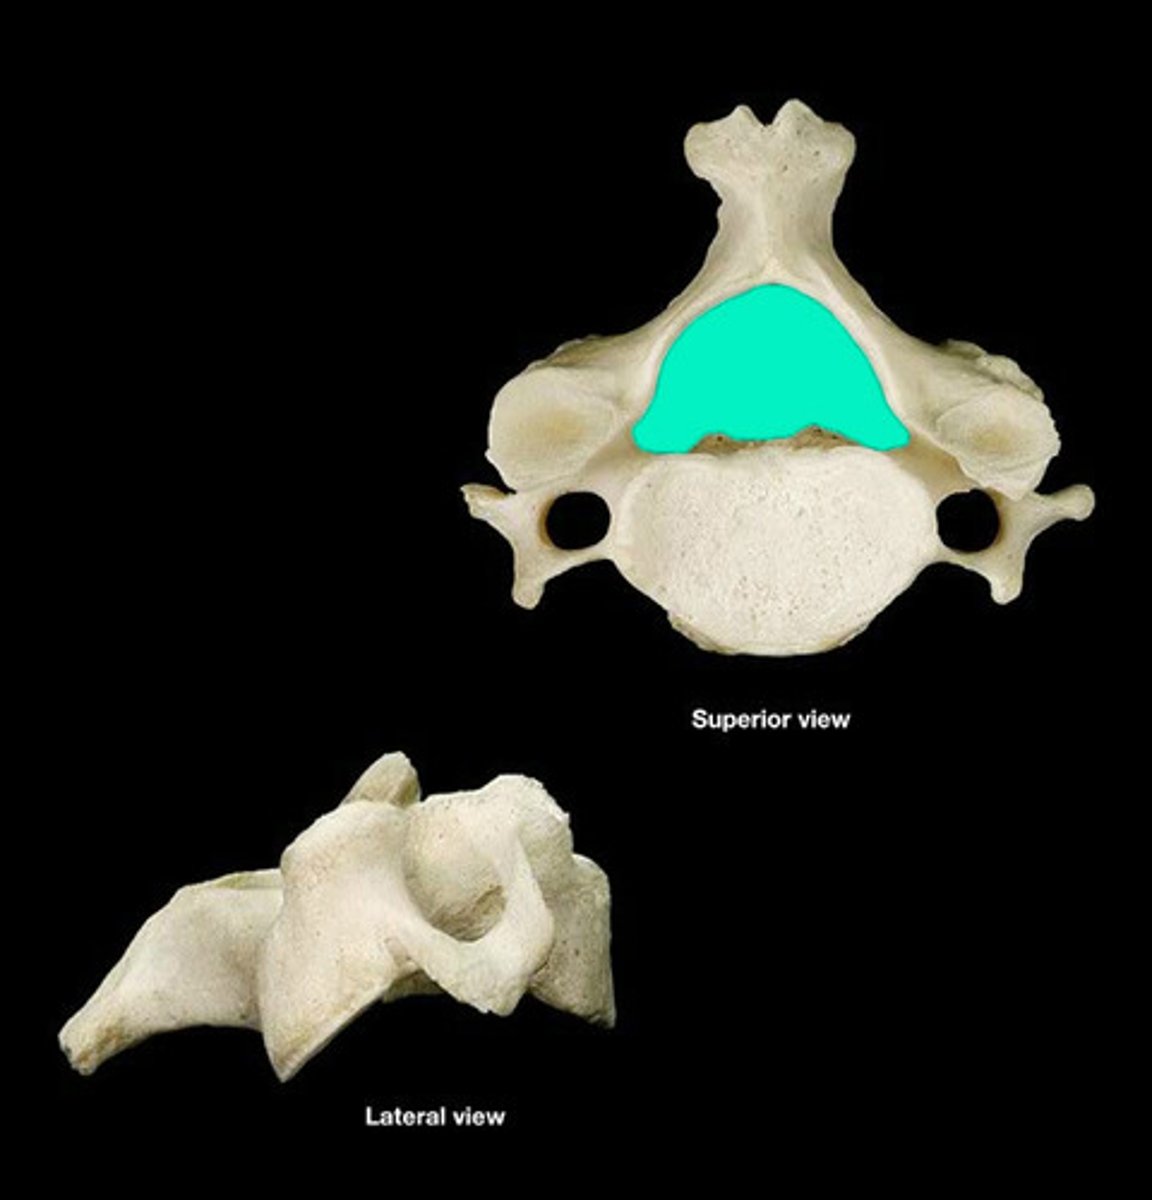

Axis (C2)

Odontoid Process